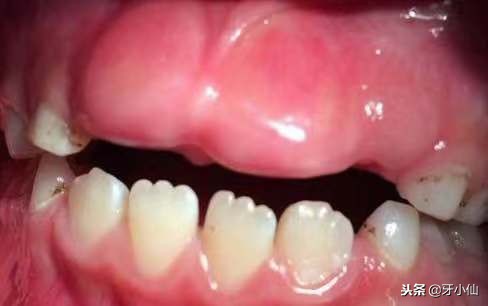

恒牙^_^犹抱琵琶半遮面图

图1: 激光助萌术后,创口小,没有出血图

图2:术后第二天,恒牙萌出

图3:术后第七天,恒牙白白哒